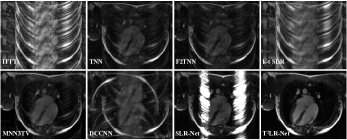

We evaluate the T2LR-Net with OCMR dataset in two sampling patterns, i.e., pseudo-radial [29] with the sampling trajectory being on the Cartesian grid and variable density random sampling, and three different sampling cases are considered at each sampling pattern, where 8, 16, 30 lines are involved under radial sampling pattern and 8, 10, 12 acceleration factor (acc = the number of the sampled pixels / the total number of pixels) under the variable density random sampling pattern, as shown in Table 1, which lists the average SNRs of the different methods under these six different sampling cases on the test dataset of the OCMR. Fig.3 shows the reconstruction results of a certain test image of the OCMR dataset for the different methods under the pseudo-radial sampling pattern [29] with 16 lines, while Fig.4 shows the results on the variable density random sampling pattern with the acceleration factor of 0.125. The first row of the figures shows the reconstruction images of the different methods, and the second row shows the enlarged view of the heart regions marked by the orange box. The first image in the third row displays the sampling mask, while the other images show the reconstruction error maps w.r.t. the different methods. The fourth row and the fifth row show the x-t images indicated by the blue dot line and their reconstruction error maps. We also evaluate our proposed network on the TCMR dataset in the same six different sampling cases and shows the average reconstruction SNRs in Table 2. The visualization results of a certain image in the test dataset of TCMR are shown in Fig.5.

Refer to caption

Fig. 3: The OCMR reconstruction results of different methods (TNN, F2TNN, k-t SLR, MNN3TV, DCCNN, SLR-Net and the proposed T2LR-Net) under the pseudo-radial sampling pattern [29] with 16 lines. The first row shows the reconstruction images of the different methods, and the second row shows the enlarged view of the heart regions marked by the orange box. The first image in the third row displays the sampling mask, while the other images show the reconstruction error maps w.r.t. the different methods. The fourth row and the fifth row show the x-t images indicated by the blue dot line and their reconstruction error maps. The reconstruction SNRs of different methods are listed in parentheses.